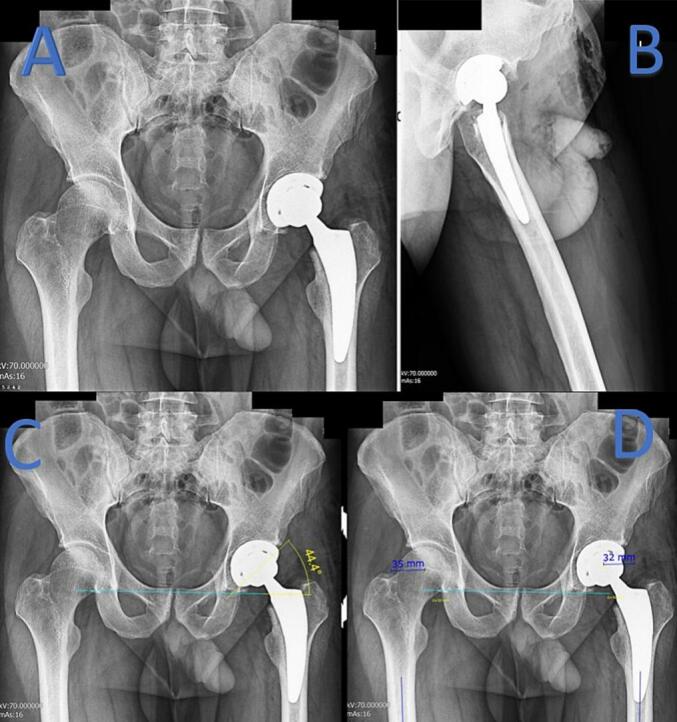

Case presentation: A 44-year-old male with femoral head avascular necrosis underwent left total hip arthroplasty. An epidural catheter was placed at the L2/3 level for postoperative pain management without complications. Two days postoperatively, the patient developed right-sided femoral nerve palsy. MRI scans revealed no spinal cord compression or hematoma. The patient's neurological symptoms began to improve five days after surgery and fully resolved by the eighth postoperative day without intervention.